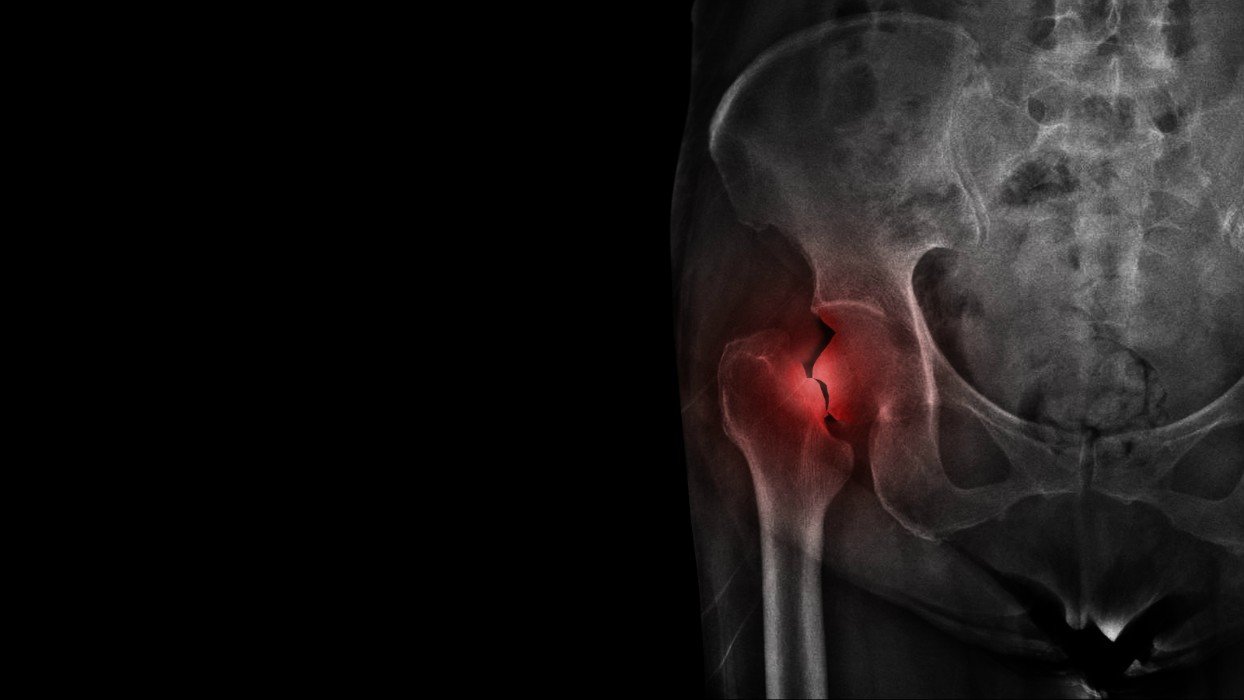

Le tabagisme est associé à un risque plus élevé de souffrir d’une fracture des os. Une nouvelle recherche a pu identifier deux pathologies provoquées par cette mauvaise habitude qui aident à prédire les risque de fracture d’un fumeur.

Dans l’article paru dans la revue scientifique Journal of Bone and Mineral Research, Les auteurs expliquent : "les fractures de la hanche sont associées à une morbidité et une mortalité significatives chez les fumeurs atteints d'une maladie pulmonaire, mais on ne sait pas si des facteurs spécifiques aux poumons sont associés au risque de fracture”.

Ils ont ainsi étudié les dossiers de 9187 adultes fumeurs ou anciens fumeurs pendant un peu plus de 7 ans en moyenne. Au total, 361 nouvelles fractures de la hanche ont été rapportées.

Plusieurs facteurs de risques, déjà associés à ce trouble, ont été confirmés : un âge avancé, être une femme, l'ostéoporose, une fracture antérieure de la colonne vertébrale ou de la hanche, la polyarthrite rhumatoïde et le diabète. Le travail d’analyse mené par les scientifiques a permis d’identifier des facteurs de risques spécifiques aux poumons. Le premier est les exacerbations fréquentes (augmentation des symptômes respiratoires : essoufflement, toux, expectoration) de bronchopneumopathie chronique obstructive (ou BPCO). Le second est un emphysème significatif, des pathologies liées au tabac.

Les fractures de la hanche : ce qu’il faut savoir

Les factures de la hanche peuvent survenir à plusieurs niveaux de cet os :

• l’extrémité supérieure arrondie (ou tête) du fémur ;

• sur la partie étroite du fémur juste en dessous de la tête (col) ;

• vers les renflements, juste en dessous du col.

Les personnes âgées sont les principales victimes. L’atteinte des os de la hanche a le plus souvent eu lieu lors d’une chute mineure, surtout si le patient souffre d’ostéoporose.

Les fractures de la hanche sont très douloureuses. Par ailleurs, le malade peut aussi être dans l’incapacité de marché, si les os cassés se sont séparés.

Selon des données statistiques, on enregistre une fracture liée à l'ostéoporose toutes les 30 secondes en Europe.

Une fracture de la hanche se soigne avec la chirurgie. Les hanches fracturées sont soit réparées, soit remplacées par une prothèse.